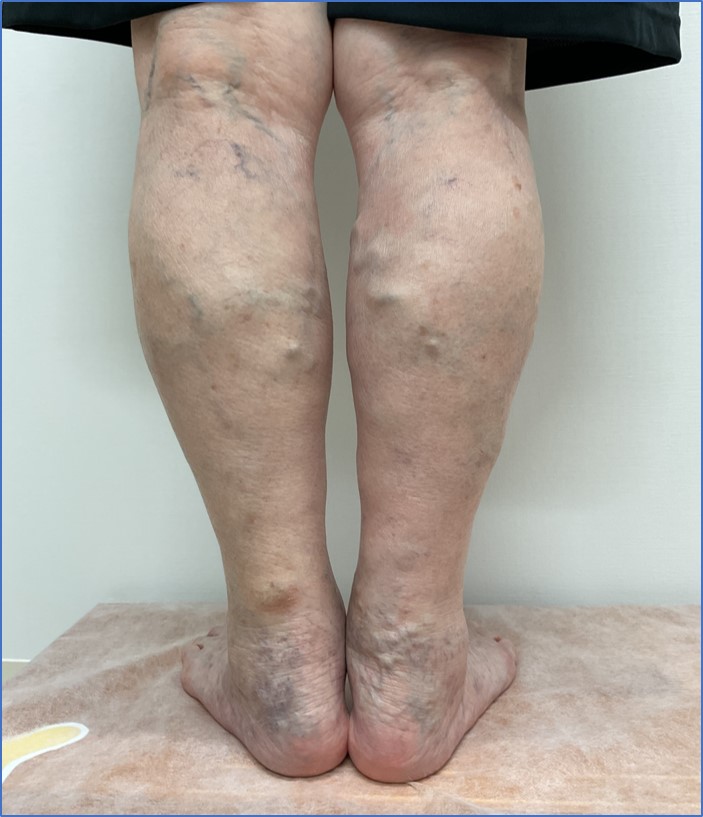

術前

術後